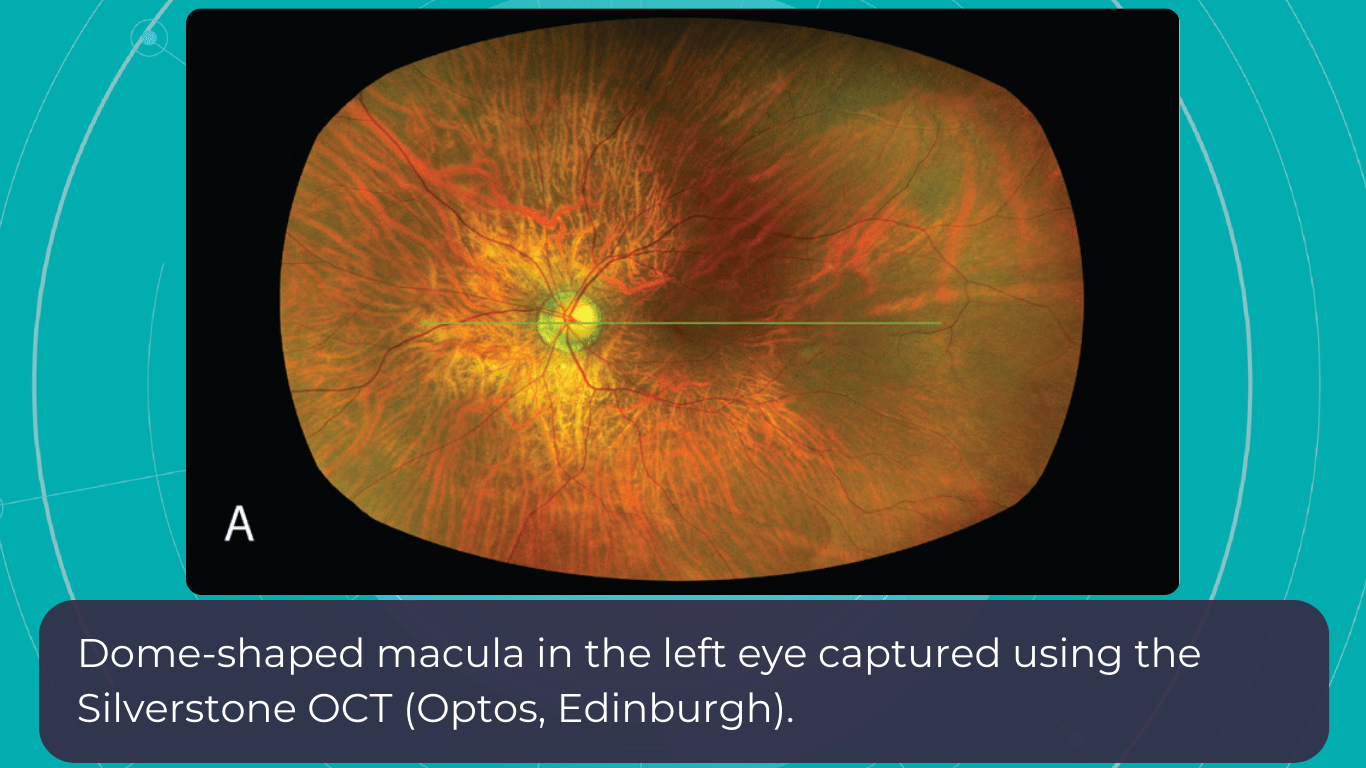

New Tech in Optometry: En-face OCT

En-face OCT in current systems is based on software reconstruction of OCT images. Image slices are selected retrospectively from full recorded volumes or calculated by depth projection along specific depth ranges, enabling three-dimensional data visualization in a fundus projection. This technique allows the projection of specific retinal and/or choroidal layers at a given depth onto an en-face view.

While we are more accustomed to working with cross-sectional images (B-scans), microstructural changes and the retinal and choroidal vasculature morphology are challenging to evaluate using B-scans alone. En-face OCT offers numerous advantages, including the ability to precisely localize lesions within specific subretinal layers using their axial location on OCT cross-sections and to register projected OCT images to other fundus imaging modalities using retinal vessels as landmarks.

Currently, en-face OCT is being applied to various specialized areas within the eye, encompassing the anterior segment, glaucoma, infectious diseases, and the retina.